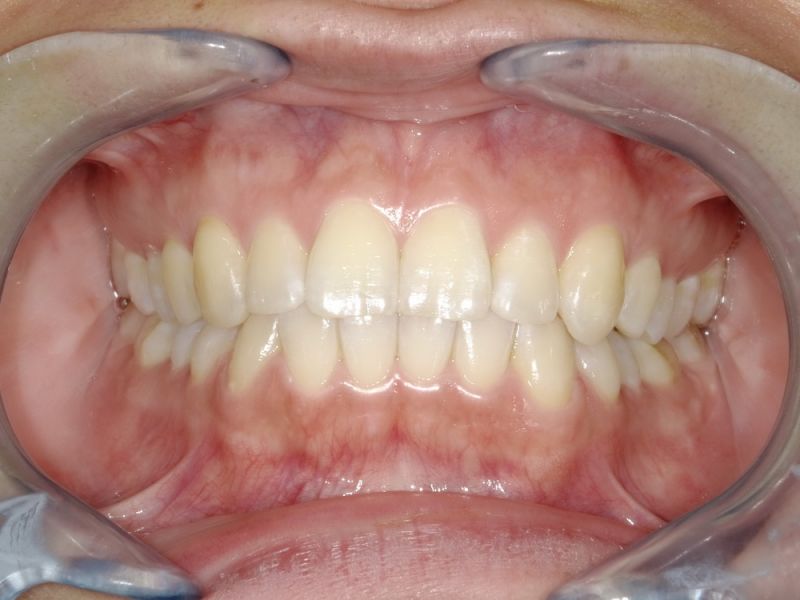

Es erfolgen die Maßnahmen der funktionellen Erstuntersuchung und die Herstellung und Eingliederung eines adjustierten Aufbissbehelfs zum Nachweis einer CMD.

Es erfolgen die Maßnahmen der klinisch manuellen Erstuntersuchung und nachfolgend die Maßnahmen zu Herstellung und Eingliederung eines adjustierten Aufbissbehelfs